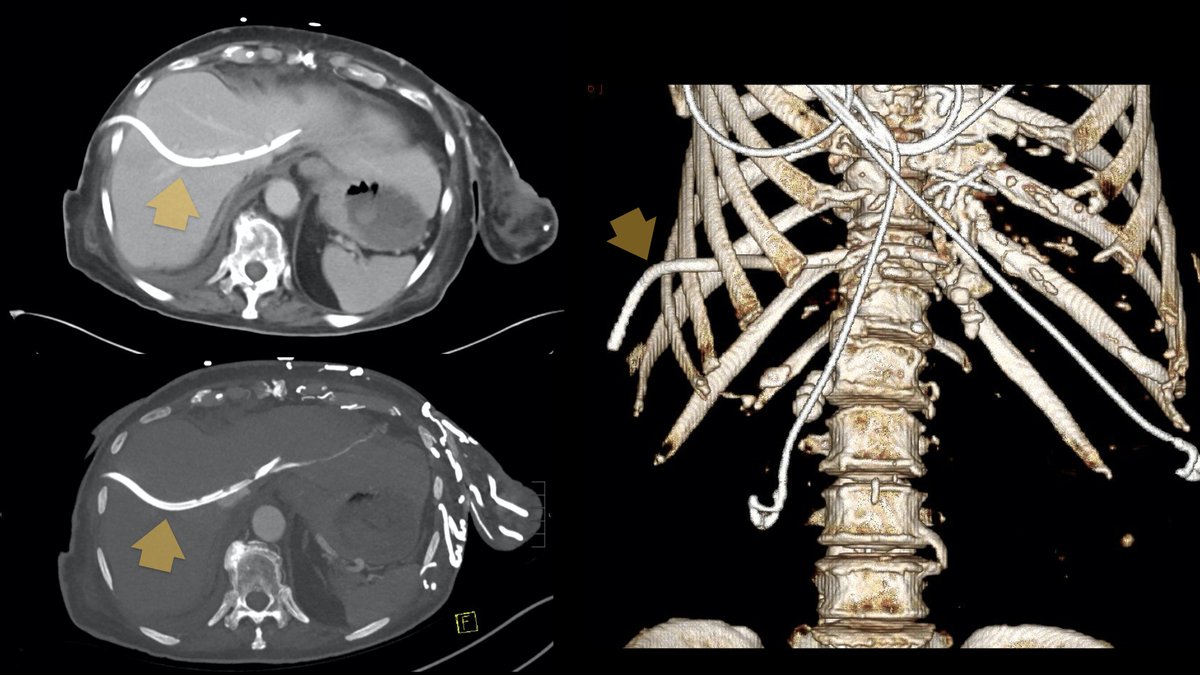

23-year-old female patient with incidental solid right adnexal mass. Small clue... it is smiling at you! 😁 Diagnosis? Next step? Brigham and Women's Radiology FOAMrad SAR Resident and Fellow Section Future Radiology Residents ARRS Abdominal Radiology CBR #MedEd